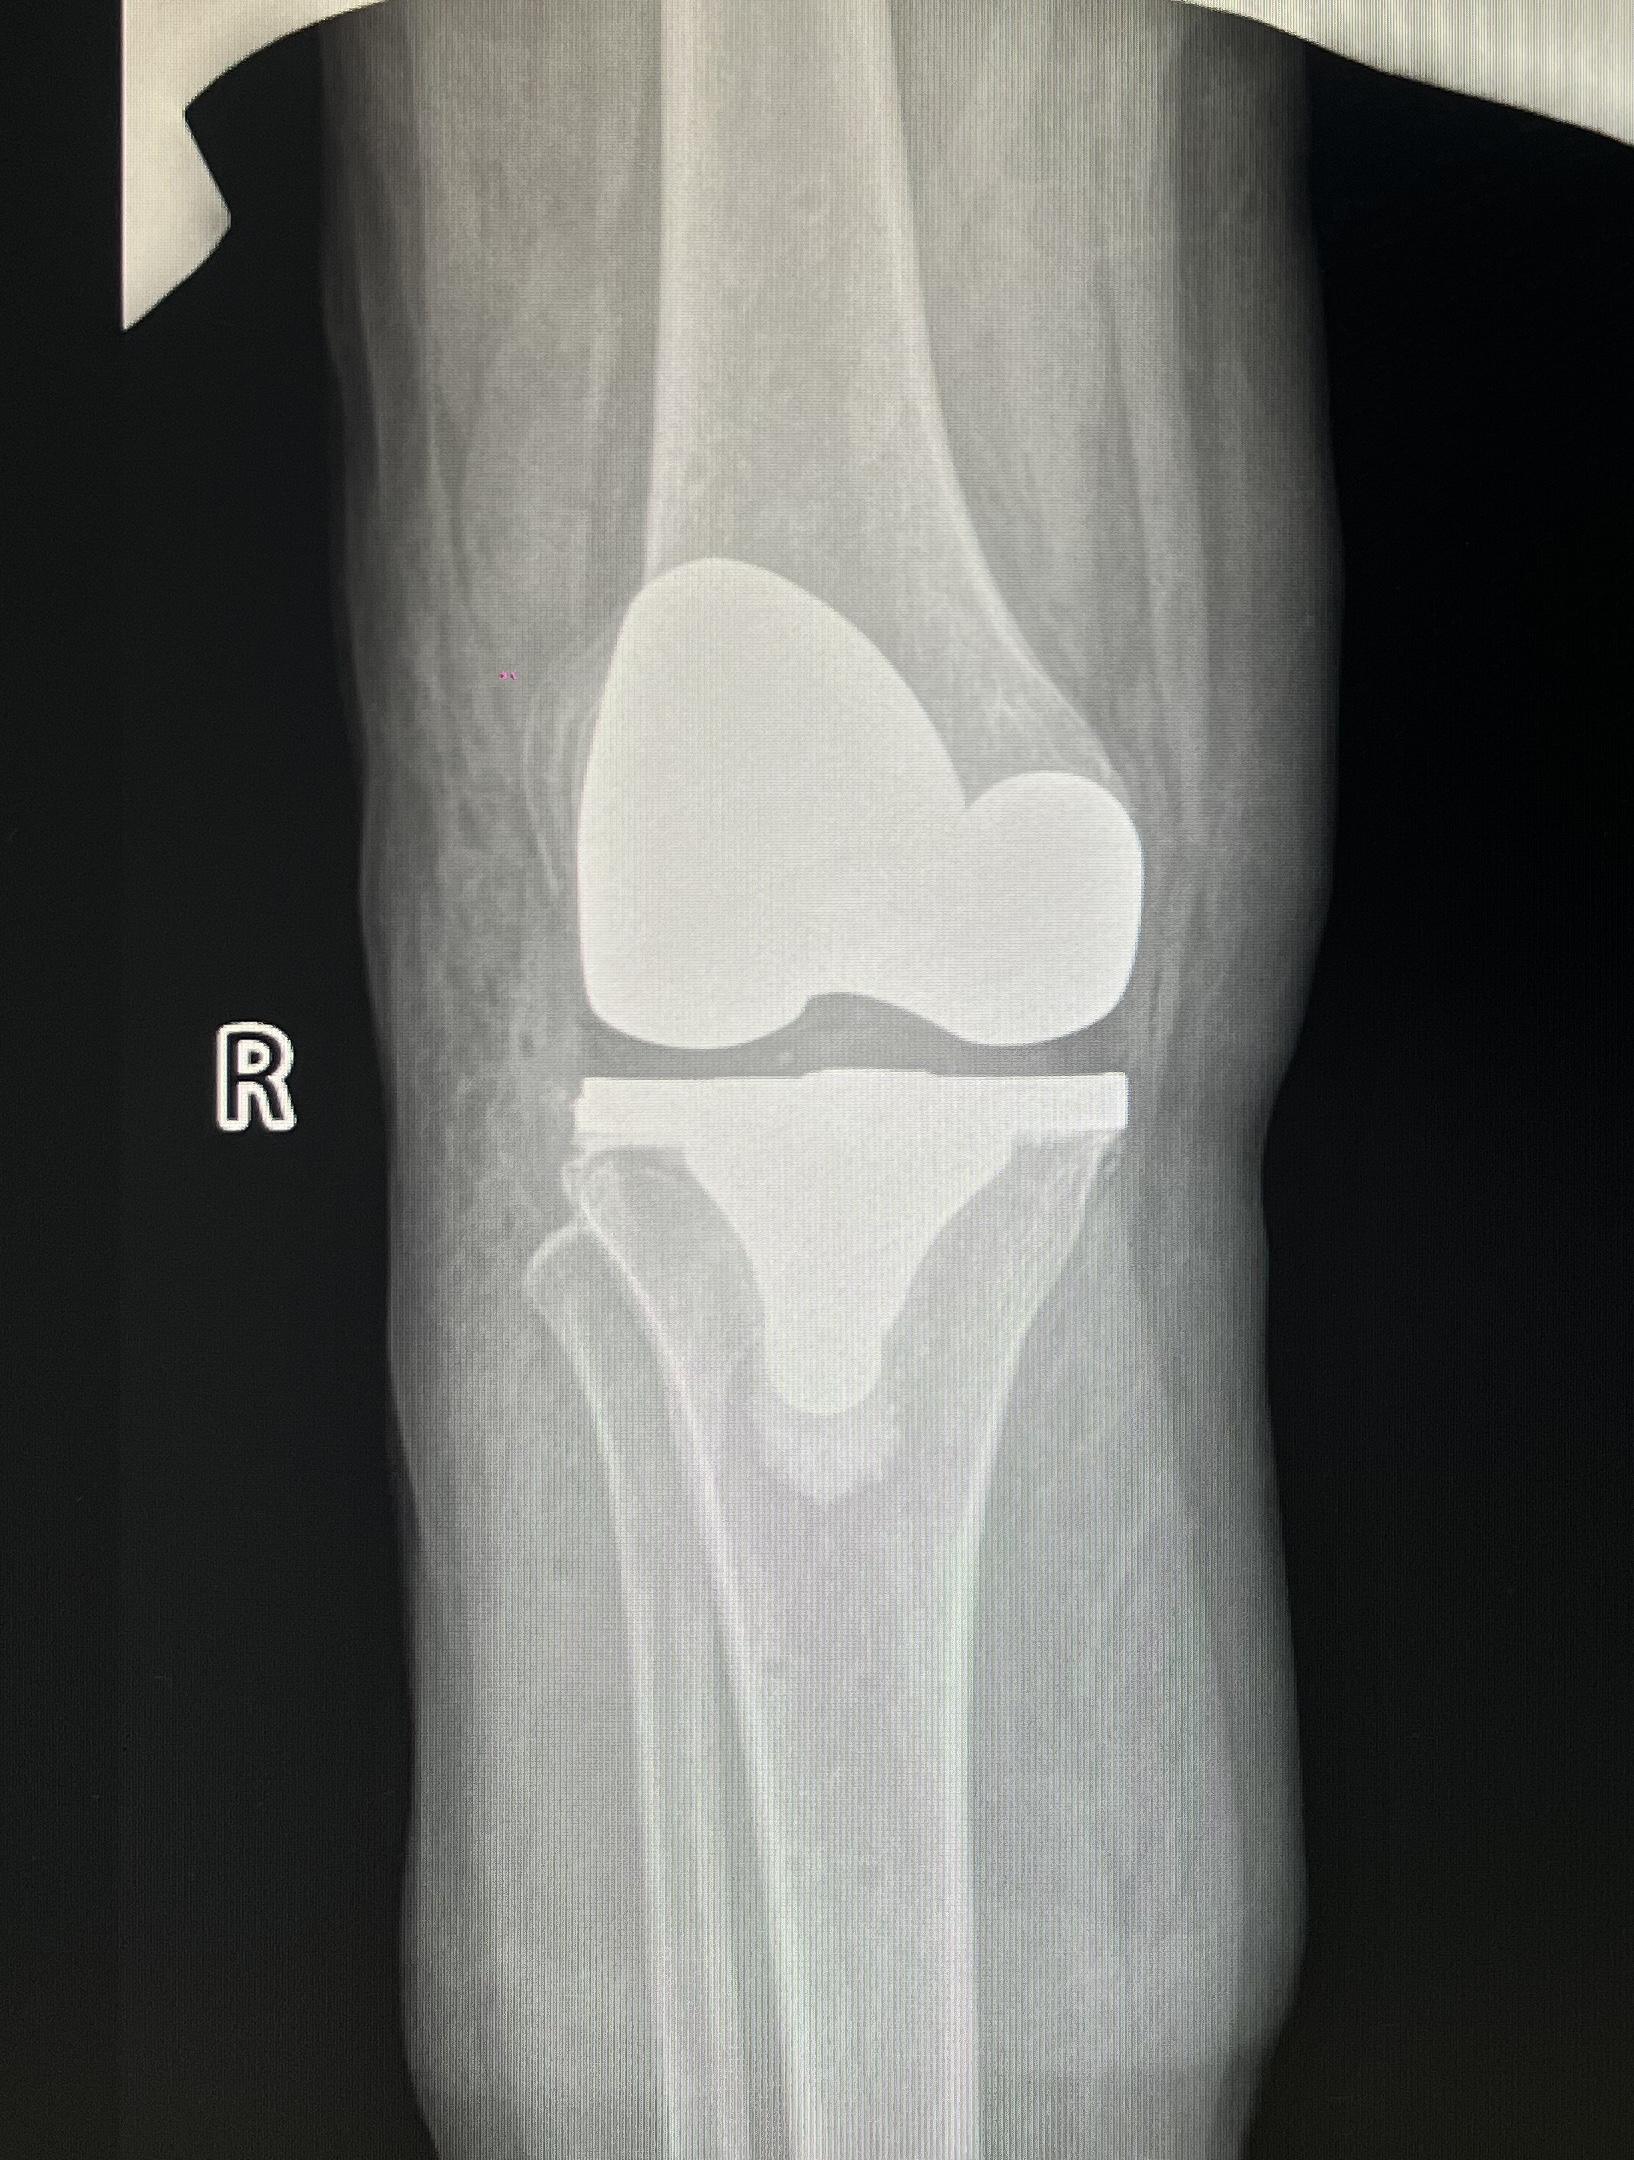

▲患者術(shù)后膝關(guān)節(jié)正位片(左) 患者術(shù)后膝關(guān)節(jié)側(cè)位片(右)

整個(gè)手術(shù)流程高效快捷,術(shù)中出血量?jī)H200毫升。與傳統(tǒng)膝關(guān)節(jié)置換術(shù)相比,鴻鵠®機(jī)器人能夠避免術(shù)中的髓腔定位,術(shù)中無髓內(nèi)桿植入,大大降低了出血量以及手術(shù)損傷,減少術(shù)后并發(fā)癥的發(fā)生,有助于患者盡早恢復(fù)。術(shù)后測(cè)量顯示,實(shí)際截骨量、下肢力線都與術(shù)前規(guī)劃的數(shù)值完全一致,實(shí)現(xiàn)了TKA手術(shù)更精準(zhǔn)、安全、高效的完成。

由于患者雙膝疼痛難忍,行走功能受限,飽受煎熬,已嚴(yán)重影響了生活質(zhì)量。為防止情況進(jìn)一步惡化,經(jīng)團(tuán)隊(duì)精確研判和綜合考量,薛勇主任和黎志超主任與患者及家屬充分溝通后,考慮使用鴻鵠®骨科手術(shù)機(jī)器人輔助實(shí)施右側(cè)全膝關(guān)節(jié)置換術(shù),以解除患者膝關(guān)節(jié)疼痛,糾正膝關(guān)節(jié)畸形并使其獲得長(zhǎng)期穩(wěn)定。全膝關(guān)節(jié)置換術(shù)是骨科大手術(shù),術(shù)中可能產(chǎn)生靜脈損傷、靜脈血流停滯及血液高凝狀態(tài)等誘發(fā)靜脈血栓栓塞癥(簡(jiǎn)稱VTE)的危險(xiǎn)因素,且接受這類手術(shù)的患者通常存在年齡較大、手術(shù)修復(fù)及術(shù)后需制動(dòng)等因素,VTE的危險(xiǎn)度較高。但在鴻鵠®骨科手術(shù)機(jī)器人的輔助下,手術(shù)全程高效流暢,通過術(shù)后測(cè)量,實(shí)際截骨量、下肢力線都與術(shù)前規(guī)劃完全一致,充分發(fā)揮了鴻鵠®骨科機(jī)器人輔助手術(shù)精準(zhǔn)度高、安全性強(qiáng)的優(yōu)勢(shì),將手術(shù)創(chuàng)傷降到最低,有效避免了VTE等并發(fā)癥。